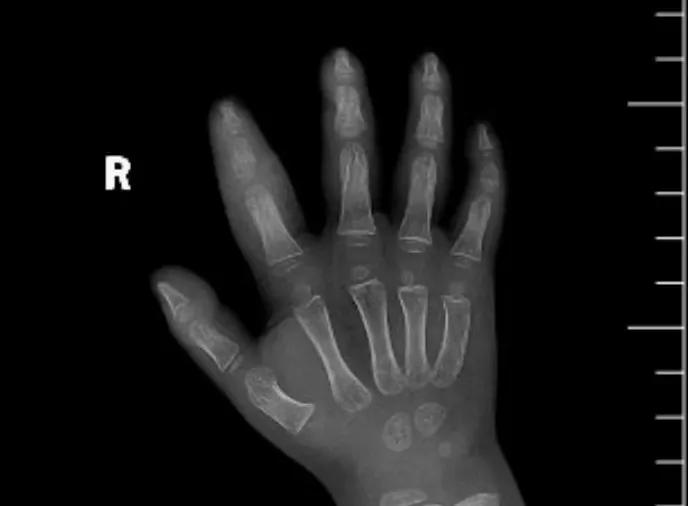

近日,市二院顯微外科接診一名3歲半的小患者,被玉米葉割傷右食指,因家長疏忽大意,導(dǎo)致一個小小的傷口竟然發(fā)展成了骨髓炎。來院時患兒右食指腫脹明顯,既不能伸也不能彎,皮膚發(fā)燙,疼得哇哇大哭。

第三天開始,月月哭鬧不止,一直說手疼,怎么哄也不行,于是在當(dāng)?shù)蒯t(yī)院治療了10來天,然而月月的手指依然腫得像個胡蘿卜,疼痛感依然存在。此時,月月的媽媽才覺得事情不大對勁,于是經(jīng)過打聽,慕名來到市二院顯微外科。入院后,經(jīng)檢查發(fā)現(xiàn),月月的右食指骨質(zhì)有侵蝕,骨骺有缺損,甚至?xí)绊懸院笫种傅陌l(fā)育。聽到這個消息,月月媽媽感覺心都揪住了。

隨后,經(jīng)顯微外科團隊充分的討論,制定了科學(xué)細(xì)致的治療方案,為月月做了感染灶清除及手指的開放引流,并留取了標(biāo)本做細(xì)菌培養(yǎng),為進一步的合理用藥提供依據(jù)。經(jīng)過兩周的治療,月月的手指終于順利消腫愈合,并且手指功能活動良好。說起這一個多月的煎熬,月月媽媽不禁落淚,但總算是治愈了,笑容又重新回到她們一家的臉上。